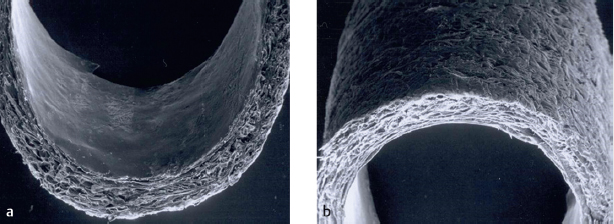

Commercially available, absorbable nerve conduits provide a noncollapsible scaffold for nerve reconstruction that features excellent availability without the disadvantages of donor site morbidity. The use of nerve conduits also provides a simplified means of reconstruction which is arguably superior to autogenous nerve grafting. Multiple size options are available, and nerve conduit walls are semipermeable, which helps in maintaining the influx of nutrients and other factors required for optimal nerve regeneration (► Fig. 21.2).